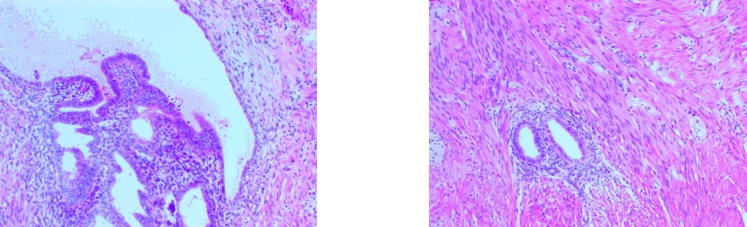

图2 直肠EUS-FNA组织学检查可见少许子宫内膜腺体及间质(HE×200) A:ER阳性;B:PAX8阳性Fig.2 Histological examination of rectal EUS-FNA showing scant endometrial glands and stroma (HE×200) A: ER positive; B: PAX8 positive